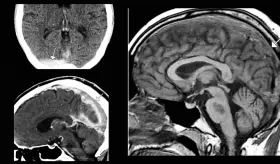

Este caso destaca la importancia de considerar etiologías supratentori...

La paciente presentaba múltiples factores de riesgo incluyendo uso de ...

La cefalea posparto afecta hasta un tercio de las mujeres en la primera semana tras el parto. Aunque la mayoría corresponden a cefaleas primarias benignas, existe una proporción significativa de etiologías secundarias potencialmente graves

Los hallazgos en resonancia magnética mostraron el patrón característico de edema vasogénico en regiones parieto-occipitales bilaterales.